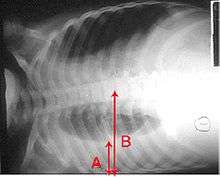

A pleural effusion appears as an area of whiteness on a standard posteroanterior chest X-ray.[5] Normally, the space between the visceral pleura and the parietal pleura cannot be seen. A pleural effusion infiltrates the space between these layers. Because the pleural effusion has a density similar to water, it can be seen on radiographs. Since the effusion has greater density than the rest of the lung, it gravitates towards the lower portions of the pleural cavity. The pleural effusion behaves according to basic fluid dynamics, conforming to the shape of pleural space, which is determined by the lung and chest wall. If the pleural space contains both air and fluid, then an air-fluid level that is horizontal will be present, instead of conforming to the lung space.[6] Chest radiographs in the lateral decubitus position (with the patient lying on the side of the pleural effusion) are more sensitive and can detect as little as 50 mL of fluid. At least 300 mL of fluid must be present before upright chest X-rays can detect a pleural effusion (e.g., blunted costophrenic angles).

Massive left-sided pleural effusion (whiteness) in a patient presenting with lung cancer.